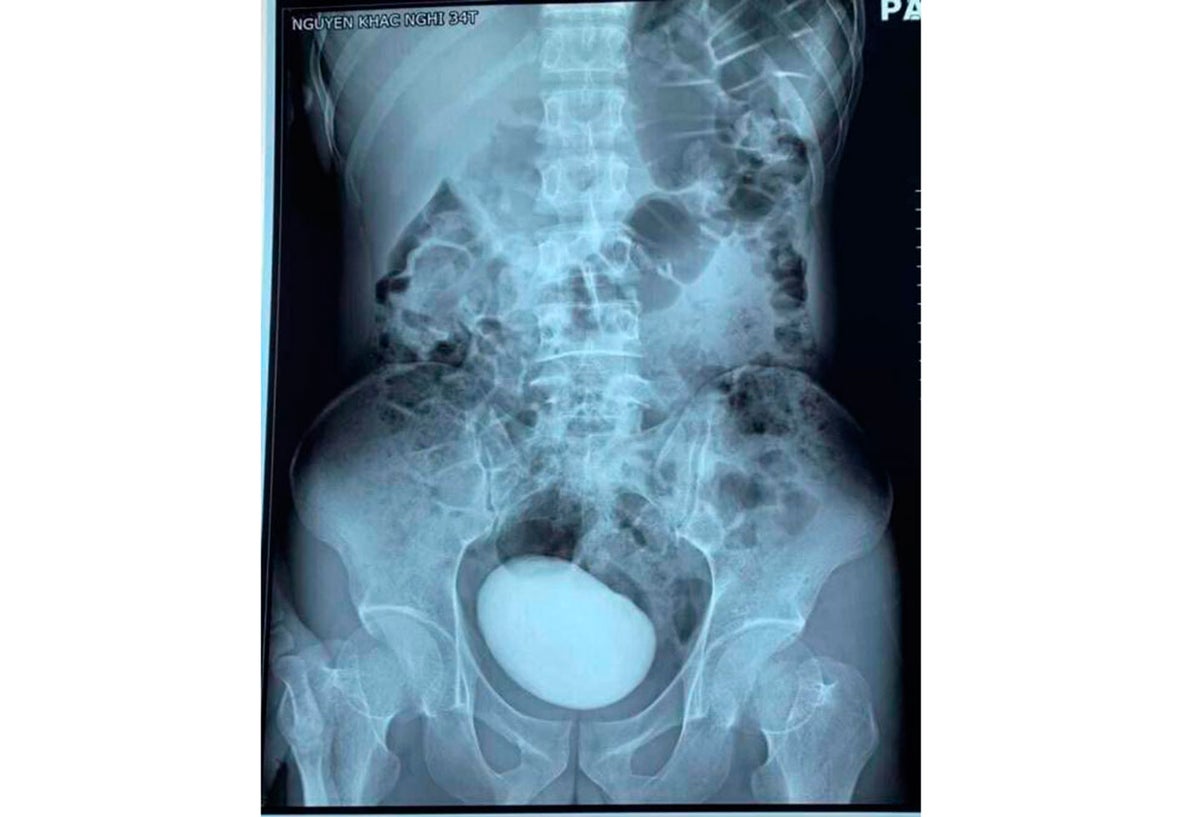

A la mujer, luego de practicarle una tomografía (CT) para tener una imagen más clara de lo que le estaba sucediendo, le fue descubierta una enorme masa que estaba en su abdomen.

De inmediato, los galenos le informaron a la mujer que debían hacerla una cirugía de urgencia para extraerle esa extraña masa. En medio de la intervención, los especialistas quedaron impactados al descubrir que se trataba un cálculo de más de diez centímetros de largo que pesaba más de 400 gramos.